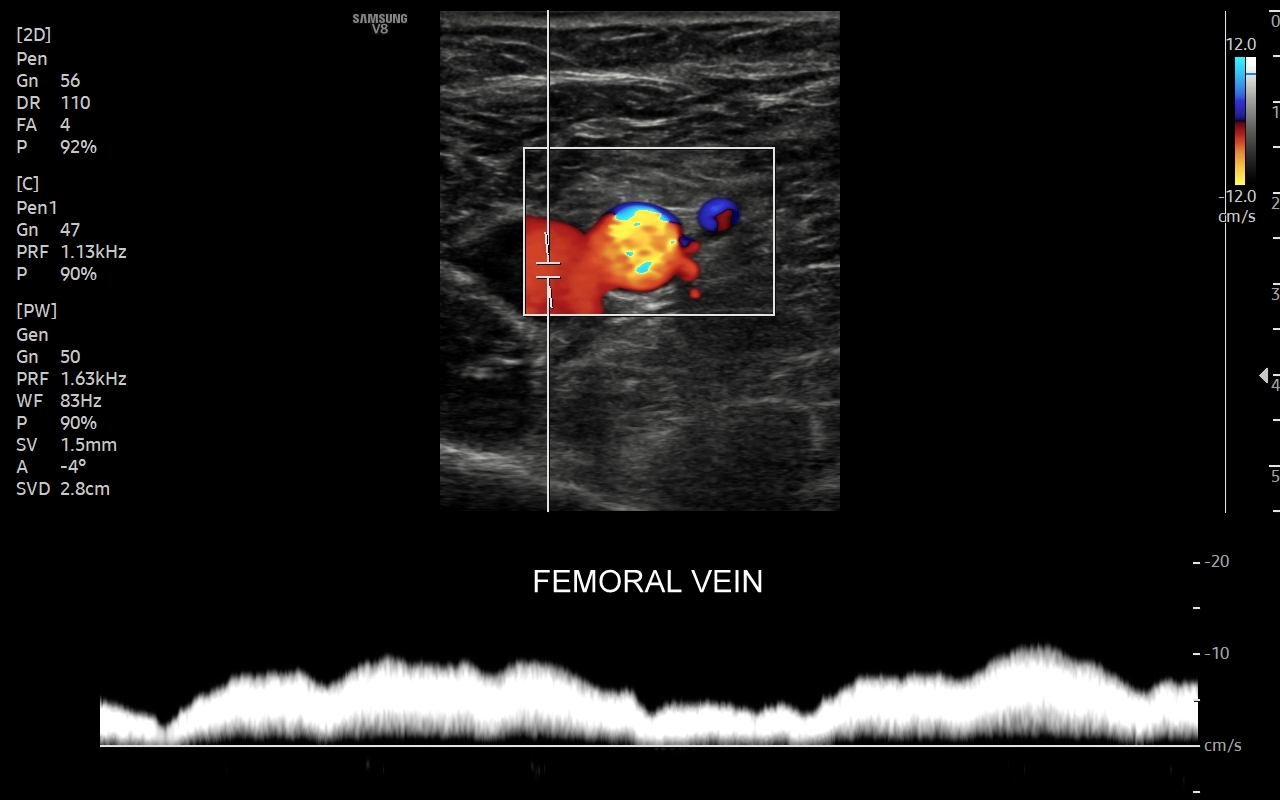

Czym jest zakrzepica żył? Zakrzepica żylna polega na powstaniu skrzepu wewnątrz naczynia żylnego i wtórnym rozwoju stanu zapalnego w okolicy naczynia. Choroba dotyczyć może układu powierzchownego żył lub żylaków, a w tym wypadku nie jest zwykle stanem niebezpiecznym; a także układu głębokiego żył, co z kolei jest stanem potencjalnie zagrażającym życiu, gdyż może sprowokować zatorowość płucną. Zakrzepica żył głębokich (ang. deep venous thrombosis DVT) częściej występuje w obrębie żył kończyn dolnych, następnie w obrębie żył biodrowych, rzadziej w żyle podobojczykowej i żyłach głębokich kończyny górnej. Przyczyny zakrzepicy żylnej są różnorodne i obejmują m. in. długie podróże, długotrwałe unieruchomienie, operacje ortopedyczne, chirurgiczne i szczękowe, urazy tkanek miękkich oraz złamania kości, genetycznie uwarunkowane trombofilie, nowotwory złośliwe, odwodnienie, infekcje miejscowe i ogólnoustrojowe. W przypadku zakrzepicy żyły podobojczykowej klasyczną jej przyczyną jest ucisk; w swojej praktyce klinicznej dr Szczepański spotkał się z zakrzepicą podobojczykową wywołaną m. in. przez ciężki plecak, wyciskanie sztangi na siłowni, czy przez uprawianie wspinaczki skałkowej. W warunkach szpitalnych zakrzepica żyły podobojczykowej lub żyły szyjnej wewnętrznej może pojawić się w wyniku zakładania cewników dożylnych. Sprawne wykrycie zakrzepicy w badaniu USG, a następnie wdrożenie odpowiedniej terapii uchronić może pacjenta przed powikłaniami ostrymi (np. zator płucny), jak i opóźnionymi (np. zespół pozakrzepowy).

Badanie USG żył kończyn dolnych najczęściej wykonywane jest w ramach diagnostyki niewydolności żył powierzchownych oraz ich objawów w postaci pajączków żylnych, żylaków kończyn dolnych, obrzęków i owrzodzeń żylnych. Kolejnym pod względem częstości wskazaniem do badania Doppler żył jest podejrzenie zakrzepicy żył głębokich kończyn dolnych, monitorowanie leczenia zakrzepicy oraz ocena jej powikłań odległych. Powikłaniem nieleczonej zakrzepicy żył głębokich może być zespół pozakrzepowy manifestujący się masywnymi obrzękami kończyny i zaburzeniami troficznymi. Badanie USG Doppler żył kończyn dolnych często uzupełniane jest oceną układu żył centralnych w miednicy i jamie brzusznej. W tych obszarach również pojawiać się mogą żylne zmiany zakrzepowe, niedrożności żył, a nawet zmiany nowotworowe.

Podczas najczęściej przeprowadzanego badania, tj. USG Doppler kończyn dolnych, oceniane są żyły głębokie oraz powierzchowne na całej długości kończyny – od stóp aż do pachwiny. Czasami mogą zaistnieć wskazania do rozszerzenia badania na wyższy poziom układu żylnego, tj. na żyły biodrowe w miednicy i żyłę główną dolną w jamie brzusznej. Badanie USG żył jest badaniem dynamicznym, tzn. oprócz oceny wyglądu żył wykonuje się różnorodne próby czynnościowe, takie jak kompresja, głębokie oddychanie, próba Valsavy, podczas których rejestruje się przepływy krwi w żyłach.

Czy USG Doppler wykrywa zakrzepicę? Tak, badanie Doppler żył jest najważniejszą metodą diagnostyczną wykrywającą zakrzepicę żył głębokich i powierzchownych. W związku z faktem, iż nieleczona zakrzepica żył głębokich może być przyczyną niebezpiecznego zatoru płucnego lub utraty kończyny badanie Doppler należy wykonać jak najszybciej w każdym przypadku podejrzenia zakrzepicy.